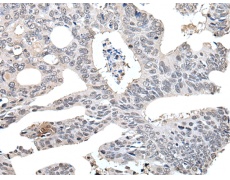

IHC positive control: |

Human colorectal cancer |

IHC Recommend dilution: |

30-150 |